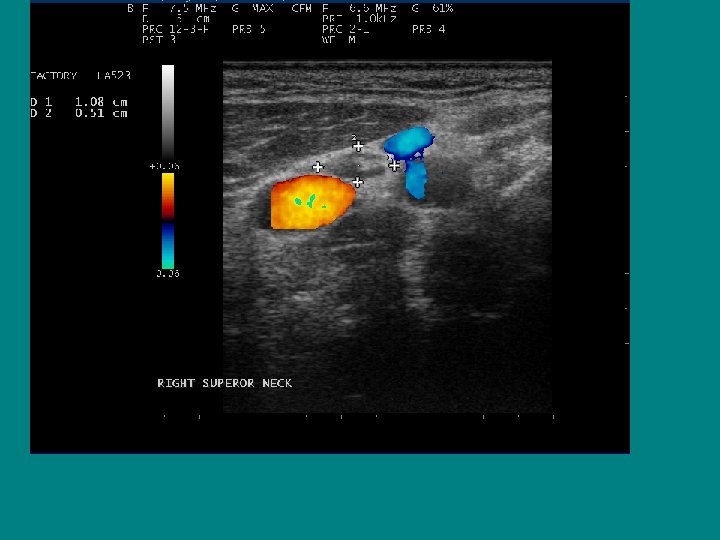

SEARCH FOR RECURRENT/RESIDUAL DISEASE • HYPOECHOIC MASS, LIKELY LYMPH NODE • AP/T 0. 7 CM !!

Ultrasound characteristics of a benign lymph node Ø Flattened or oval ( AP/T < 0. 5 Ø Echogenic Hilus Ø Hilar Flow on Doppler

Best ultrasound criteria for malignancy • Short to long axis diameter ratio of more than 0. 5 • It has 75 % sensitivity, 81 % specificity • 79 % accuracy

Does size help predict a malignant lymph node? • NO ! • Size doesn’t matter, • Border doesn’t help either

AP/T 0. 79/1. 45= 0. 54 !